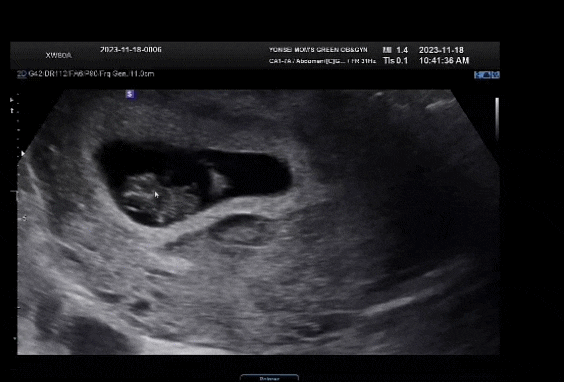

[7주 5일] 뽀록뽀록

7주 5일째 점에서 하리보 형태의 모양을 갖췄다. 이제 세포가 아닌 공식적인 태아라고 한다. 2주전 세포 크...